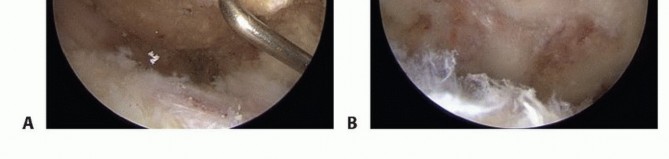

Subacromial Decompression Twenty milliliters of 1% lidocaine and 1:300,000 diluted epinephrine are injected into the subacromial space before intra-articular diagnostic arthroscopy. From the posterior portal, the cannula and trocar are redirected from the intra-articular position to the subacromial space. The correct position is confirmed by palpating the hard undersurface of the acromion with the trocar tip. Once the trocar is felt to be in the subacromial space, it is swept laterally through the subdeltoid bursa to open the subacromial space. Care should be taken to avoid sweeping the trocar medial to the AC joint, which could injure the acromial branch of the thoracoacromial artery. The arthroscope is introduced and an initial assessment of the subacromial bursa and acromial spur is done. A 5-mm skin incision is used to establish the lateral portal 2 to 3 cm distal to the midlateral border of the acromion. A 5.5-mm full-radius resector is introduced through the lateral portal. Visualization is often difficult because of the thickened and inflamed subacromial bursa. Therefore, triangulation of the arthroscope and full-radius resector must be done by palpation. Bursectomy cannot be initiated until the cutting flutes of the resector are visualized. The tip of the anterolateral aspect of the acromion is palpated with the resector to confirm the correct subacromial orientation. Bursal resection is completed in an anterior to posterior and lateral to medial direction(TECH FIG 2A). Care must be taken not to resect the highly vascular bursal tissue medial to the musculotendinous junction of the rotator cuff. A radiofrequency electrocautery device is used to coagulate any bleeding and remove the remaining soft tissue from the undersurface of the acromion, starting at the anterolateral corner of the acromion(TECH FIG 2B).

TECH FIG 2 • A. Arthroscopic bursectomy. The bursa overlying the tendinous portion of the rotator cuff must be thoroughly resected to evaluate the tendons for bursal-side rotator cuff tear. B. Soft tissue on the undersurface of the acromion is denuded with a radiofrequency electrocautery. Removing the soft tissue will expose the bony undersurface of the acromion and facilitate acromioplasty by the burr's cutting flutes. C. The acromial spur is now completely visualized. The coracoacromial (CA) ligament must be completely resected from the anterolateral acromion. Failure to do so may result in residual impingement by the CA ligament. Visualization of the undersurface fibers of the deltoid indicates a complete CA ligament resection. D. The acromioplasty begins at the far anterolateral tip of the acromion. The burr's diameter, usually 5 to 6 mm, is used to assess the initial depth of the acromial resection. The acromioplasty proceeds in 5- to 6-mm strips from anterior to posterior and lateral to medial. E. Completed acromioplasty. The undersurface of the acromion is converted to a type I morphology. Any residual ridges or rough edges can be safely smoothed with the burr in the reverse cutting position. F. View of the acromioplasty from the lateral portal. At the procedure's completion, the arthroscope should be placed in the lateral portal to assess the acromion for any residual downslope or unresected bone. The AC joint is also well visualized from this portal and may be resected or coplaned via the anterior portal. G. Coplaning of the AC joint. The posterior or lateral portal is used for arthroscopic visualization. Coplaning is performed with the burr in the anterior or lateral portal. This depth of resection is achieved anteriorly from the anterolateral corner of the acromion to the medial acromial facet of the AC joint. The depth of resection is then progressively thinned posteriorly to the midportion of the acromion such that there is a smooth zone of transition from the anterior to the midportion of the acromion(TECH FIG 2E).